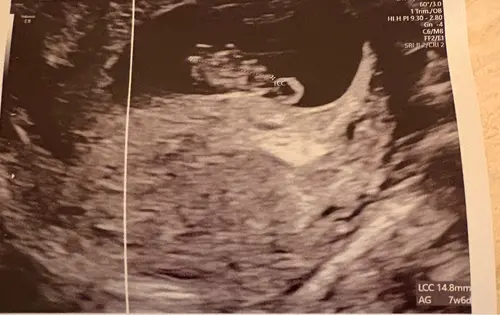

Hierbij nog eentje, dit was van mn inwendige echo. Op ongeveer iets meer dan 6 weken. 馃榿

baby boy馃挋